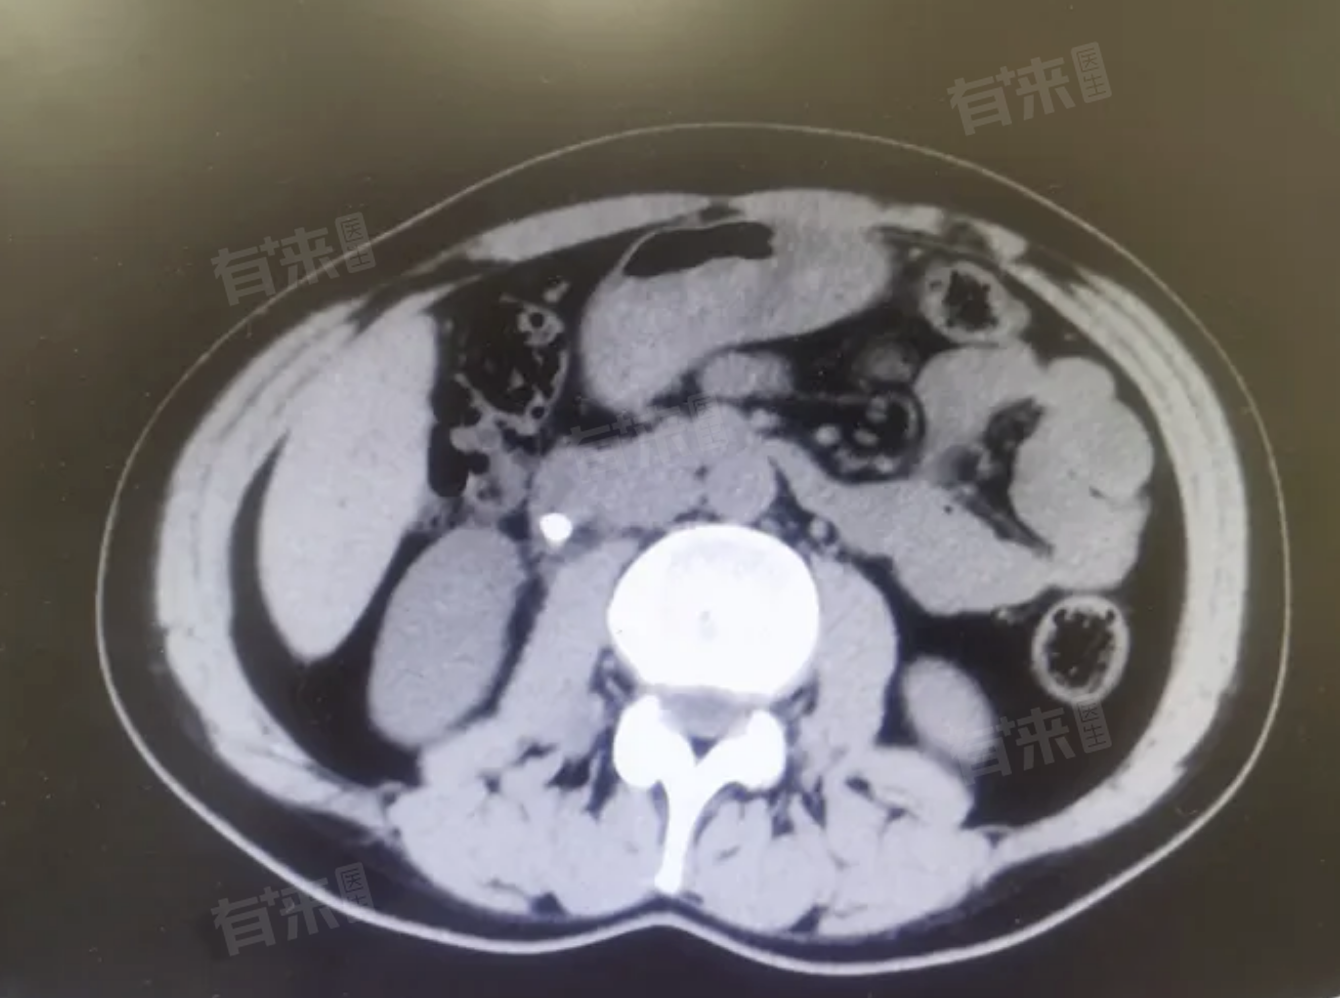

到医院后,医生给安排做了上腹部CT 检查,结果发现右侧输尿管上部有一枚大约4 - 5mm 的结石,还伴有右肾轻度积水。

血常规检查倒是没发现明显异常。结合这些症状和检查结果,医生诊断他得了输尿管结石。